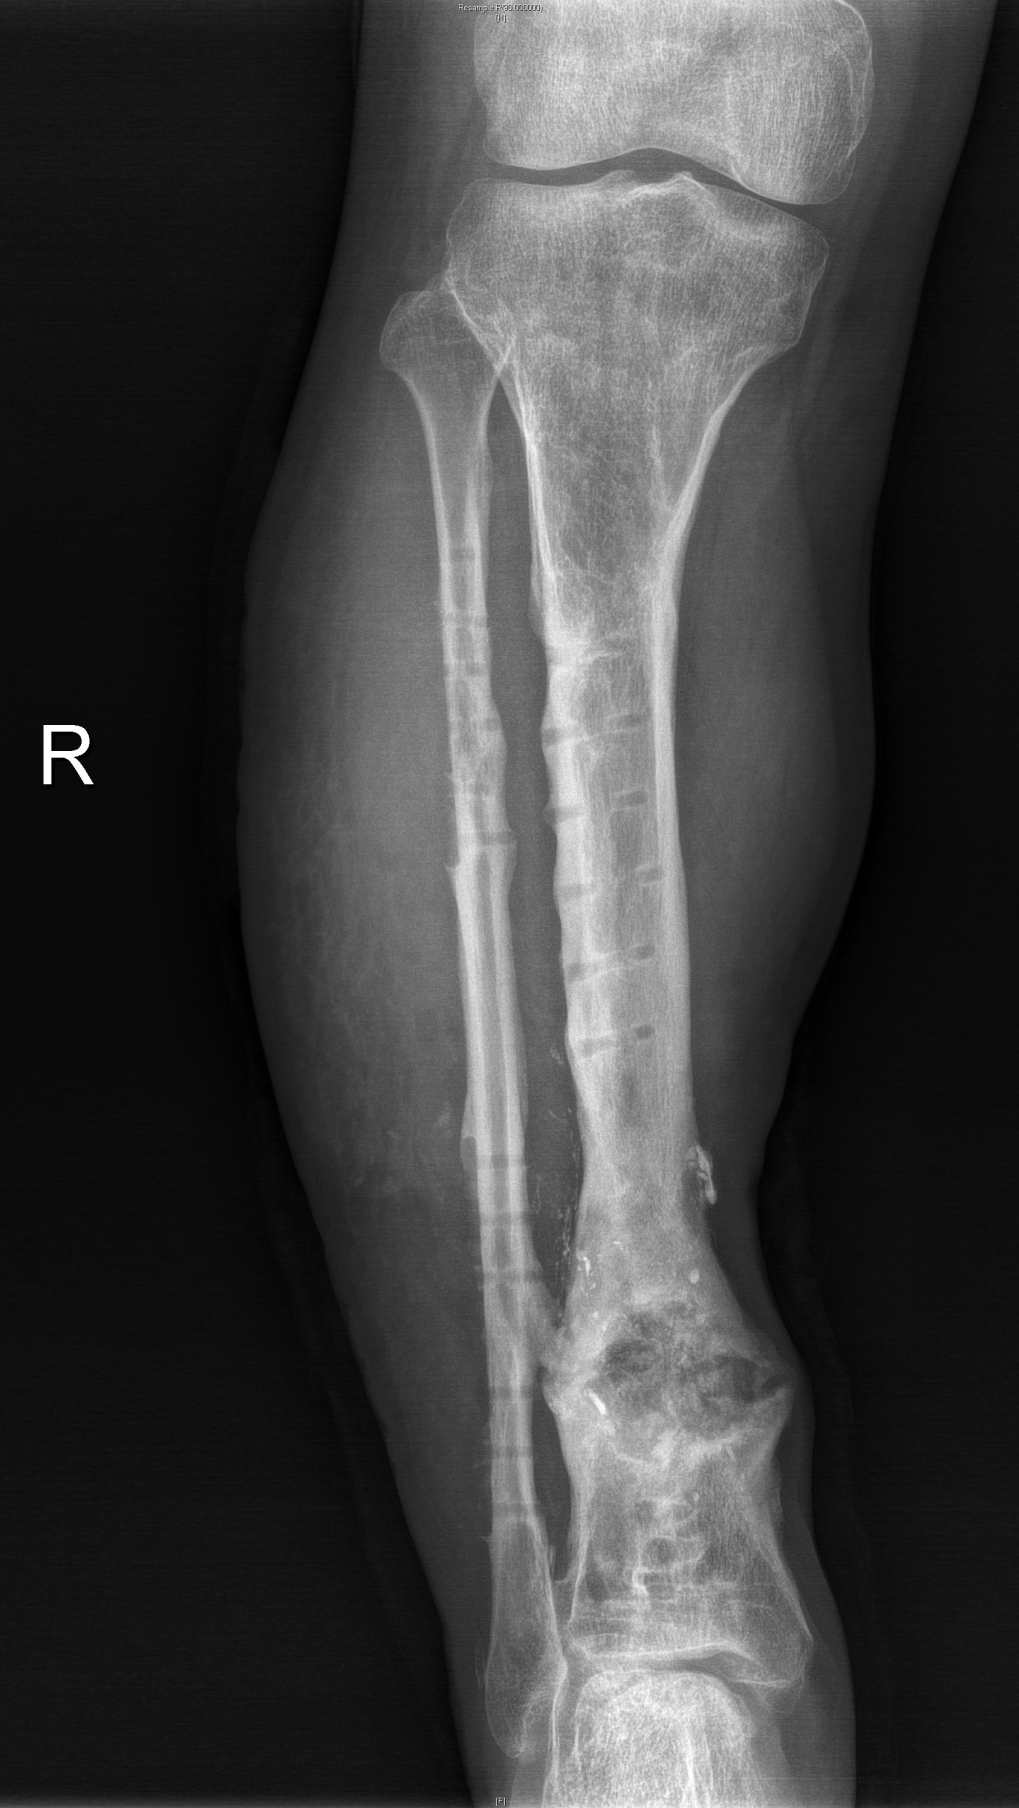

3、骨愈合

4、内固定去除

经过反复评估及推敲,徐杨主任医师决定分三步进行:首先分次清创,在保住残留血供及神经同时,彻底清创;利用长管状骨节段性缺损诱导膜再生技术(masquelet技术)修复骨缺损,最后通过肌腱转位替代、踝关节松解,恢复功能。这其中每一步都不容有失,困难重重,极具挑战。在医患通力配合下,多次按既定方案为小罗成功施行手术,小罗保住了右腿,经过近一年的正常行走生活,近日返院进行最后的钢板拆除手术。